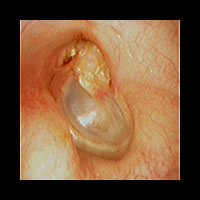

左真珠腫性中耳炎

左耳に白い真珠腫がみられます。外耳道から真珠腫をできる限り摘出しました。CTを撮影し、根治的な手術が必要でしたので、総合病院耳鼻咽喉科にご紹介し全身麻酔下に手術を行いました。

外耳道から清掃した後